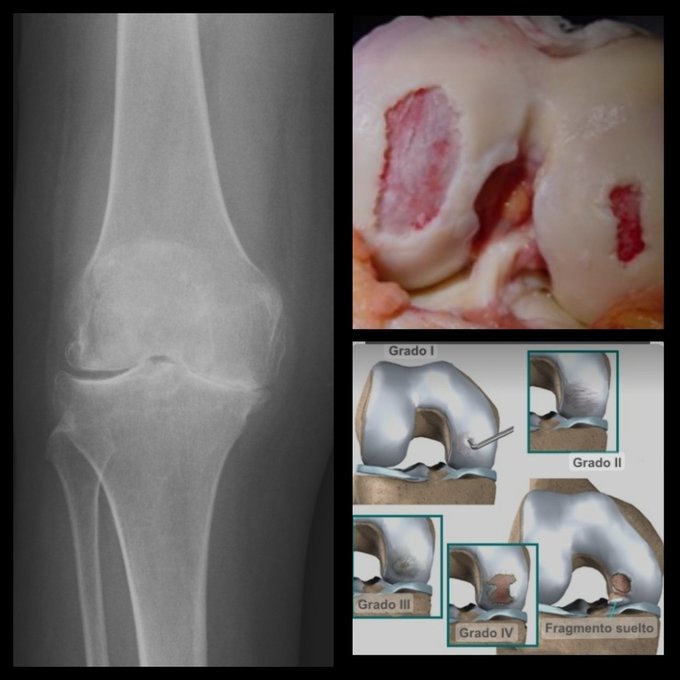

Una buena noticia. Como se sabe, la artrosis en la rodilla es una enfermedad degenerativa. Sin embargo, con un novedoso tratamiento que aplican nuestros médicos cubanos, se puede evitar que avance y reducir el dolor ligado a este mal.

Especialistas cubanos en medicina regenerativa de este centro médico, revelan que sí se puede combatir la artrosis de rodilla a través de la ozonoterapia y el plasma rico en plaquetas (PRP).

“Lo que hacemos para combatir la artrosis de rodilla es que, de manera alterna, aplicamos la terapia del ozono, la cual desinflama la articulación dañada de la rodilla y posteriormente, la restablecemos con el plasma rico en plaquetas”, afirman.